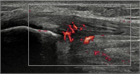

1. ジャンパー膝はジャンプやランニング動作を繰り返すスポーツ選手に好発する膝蓋腱近位部のスポーツ障害である。

1. ジャンパー膝の場合、超音波画像検査を行う事が推奨される(推奨度1)